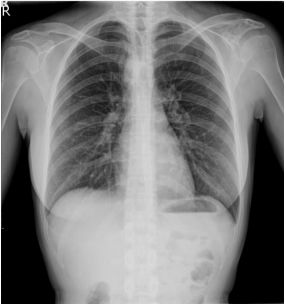

1. A 39-year-old man had this chest X-ray on his health exam. No any clinical symptoms.